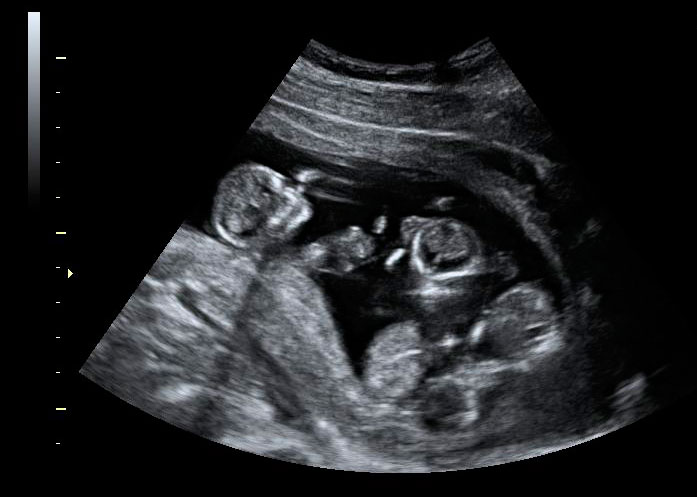

Ecografía 4D de la semana 12: Trillizos en rotación

Se observan las membranas de separación entre hermanos

La imagen ecográfica en 4D de trillizos muestra a un bebé en la parte superior y a sus dos hermanos en la parte inferior. Se pueden entrever las membranas de separación de los fetos que separan a los hermanos en dos grupos.